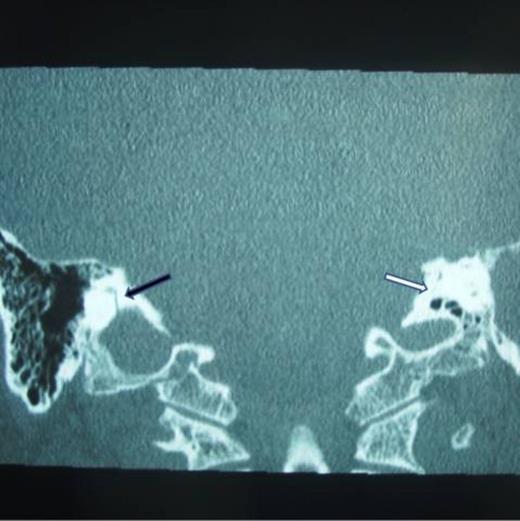

A 52 –year-old male with bilateral deafness and right facial nerve palsy presented to our clinic. The patient who was referred for consideration of cochlear implantation had a history of head injury 8 months before. An initial CT scan 2 months following his injury showed a transverse temporal bone fracture on the right side and a longitudinal one on the left side. Both cochleas appeared to be patent (Fig. 1, 2). The left ear was chosen for implantation as the injury was less severe on that side.

Right transverse fracture (black arrow) and left longitudinal fracture (white arrow)